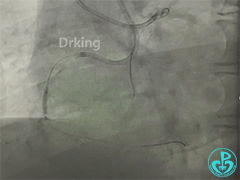

Gaia3磨进2段,进入内膜下,但微导管无法跟进。

导丝怎么扩收藏:器械难以通过的CTO病变之技术图谱_https://www.jmylbn.com_新闻资讯_第14张

微导管无法通过,球囊同样无法通过,无法行S-ADR术式。